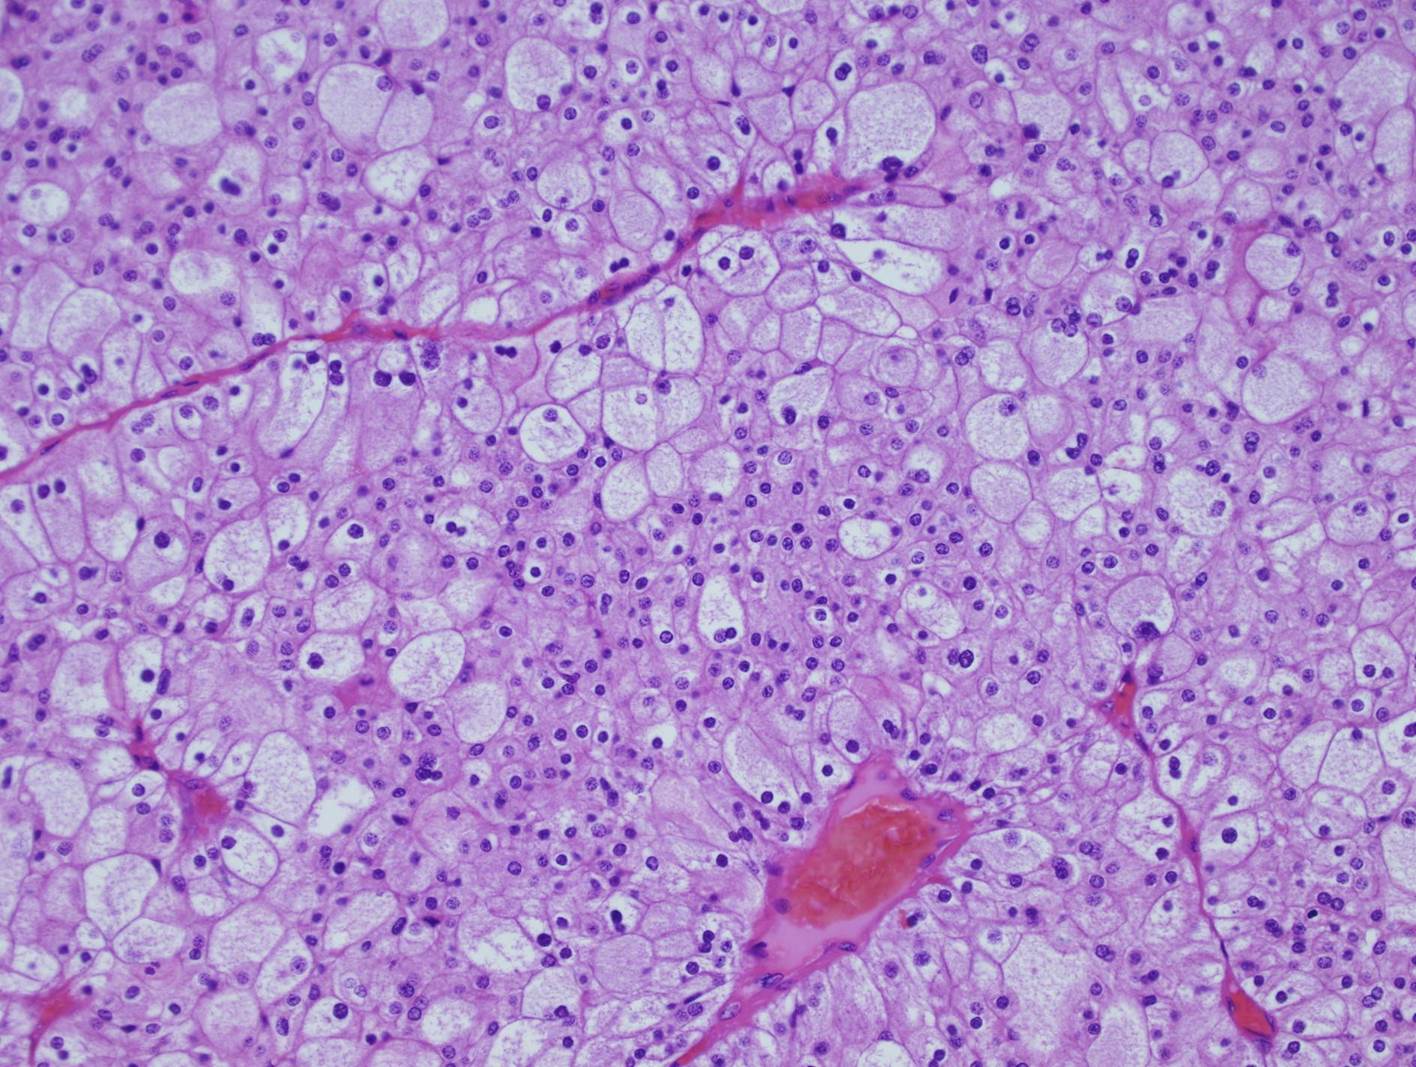

Case ID: 702

Consensus grade: I would not grade this tumor

chromophobe |

| Pathologist 17 | WHO/ISUP grade 4 | Borderline lower |

chromophobe RCC-grading? |